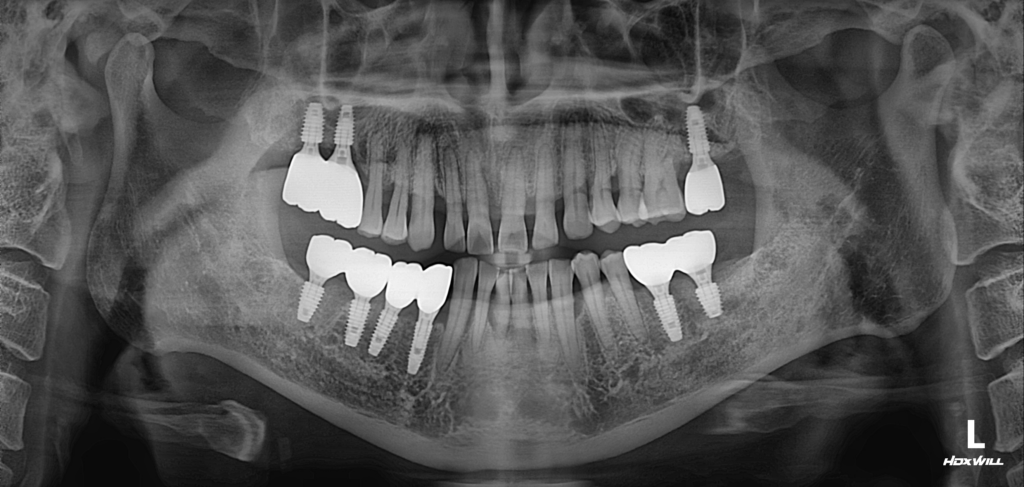

시술 전

25.06.10

해당 환자분께서는 여러 가지 구강 문제로 내원하셨습니다.

먼저 비교적 젊은 연령대임에도 불구하고 상악 치아 사이가 벌어지는 증상이 나타나면서 심미적인 부분에서 불편함을 느끼고 계셨습니다. 웃을 때 보이는 전치부의 변화가 신경 쓰여 상담을 원하셨습니다. 또한 하악 전치부에서는 치아의 동요가 관찰되었습니다. 보다 정밀한 상태를 확인하기 위해 방사선 검사를 진행한 결과, 기존에 임플란트가 식립되어 있던 부위 앞쪽 치아 주변에서 치조골이 상당 부분 소실된 모습이 확인되었습니다.

이에 따라 부위별로 다른 치료 계획을 세우게 되었습니다. 상악 전치부의 경우에는 환자분과 충분한 상담을 진행한 뒤, 심미적인 결과를 우선적으로 고려하여 보철 치료를 통해 전치부를 회복하는 방향으로 계획을 수립했습니다. 자연스러운 치아 형태와 배열을 고려하여 보철물을 제작하는 방식으로 진행하기로 하였습니다.

반면 하악 전치부는 기능적인 문제와 함께 심미적인 요소도 중요한 부위이기 때문에, 염증의 범위가 심하지 않은 경우에는 발치 후 즉시 임플란트 식립을 고려하는 치료 계획을 세웠습니다. 정확한 상태를 평가한 뒤 발치와 동시에 식립이 가능한지 여부를 판단하여 진행하기로 하였습니다.